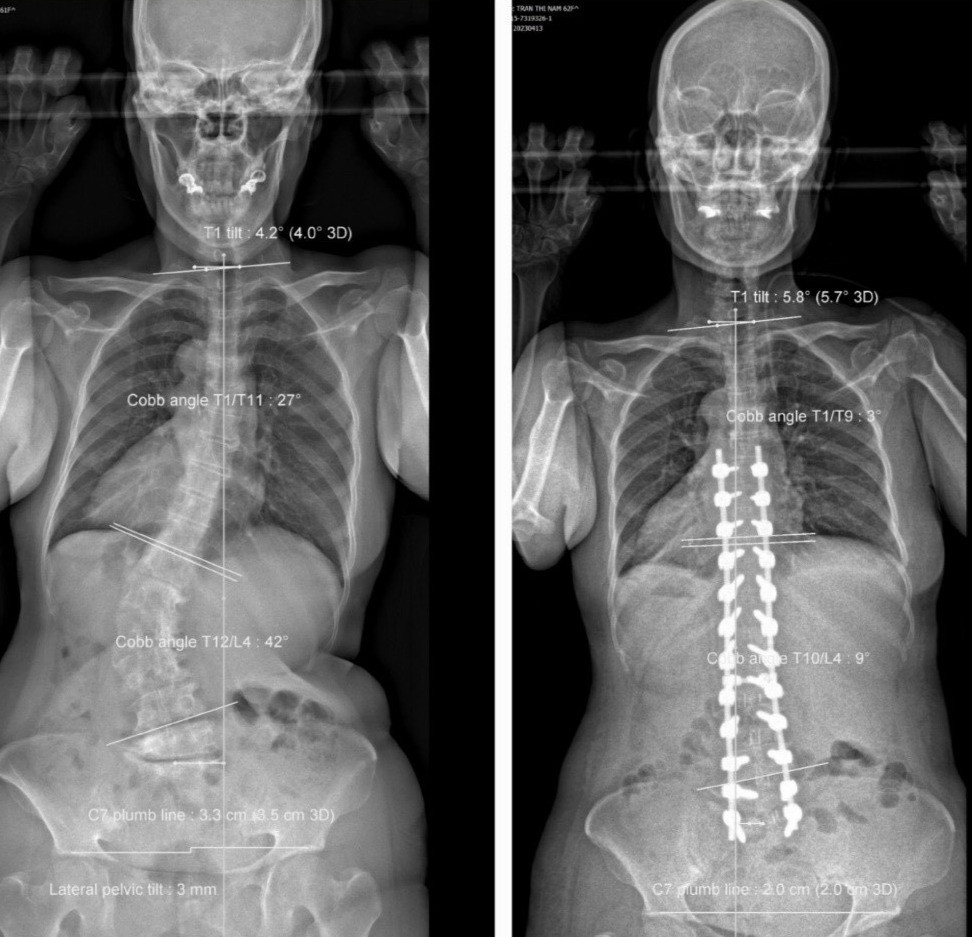

Tại Đơn vị Cột sống, Bệnh viện Trưng Vương, kết quả chẩn đoán hình ảnh bao gồm Xquang-EOS toàn thân và MRI cho thấy bệnh nhân bị vẹo cột sống ngực-lưng (từ ngực 1 đến ngực 11) 27 độ, vẹo cột sống thắt lưng (ngực 12 đến thắt lưng 4) là 42 độ, thoái hóa cột sống, còng cột sống, mất ưỡn cột sống thắt lưng, biến dạng phức hợp khung chậu - cột sống, mất thăng bằng nặng toàn bộ cột sống, đường trọng lực đổ ra trước.

Ngoài ra, bà còn bị hẹp ống sống lưng - thắt lưng nhiều tầng, chèn ép ống sống và rễ thần kinh tương ứng, thoái hóa đốt sống dạng thoái hóa mỡ, biến dạng mất độ ưỡn sinh lý cột sống thắt lưng.

Theo bác sĩ Tâm, người bệnh được chẩn đoán thoái hóa nặng cột sống thắt lưng gây biến dạng cột sống, vẹo cột sống ngực - thắt lưng, hẹp ống sống thắt lưng nhiều tầng gây chèn ép rễ thần kinh, mất thăng bằng cột sống.

Các bác sĩ đã tiến hành phẫu thuật giải ép, ghép xương, cắt đĩa đệm hàn xương liên thân đốt cột sống thắt lưng, kết hợp nắn chỉnh đường cong trước sau cột sống thắt lưng. Do đây là trường hợp khó, đòi hỏi phẫu thuật viên phải có nhiều kinh nghiệm về nắn chỉnh mà không làm tổn thương thần kinh như đứt rễ thần kinh, rách màng cứng gây liệt…

Sau ca phẫu thuật kéo dài hơn 7 giờ 30 phút, bệnh nhân cao thêm 8cm. Hiện dáng đi thẳng, người và phần đầu không còn đổ về trước khi đi hay đứng, hết đau tê hoàn toàn chân phải, chân trái còn tê rất ít, sức cơ hoàn toàn bình phục.